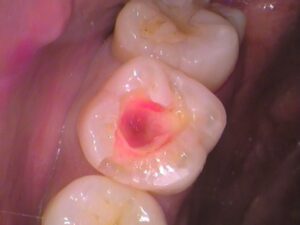

う蝕検知液という虫歯を染色するお薬を塗ってみましょう。

赤く染まっている箇所が虫歯のところです。

詰め物の中がほとんど虫歯で広がっています。

虫歯を丁寧に削り取っていきます。

その都度、虫歯を染め出して虫歯の残っている所を確認します。